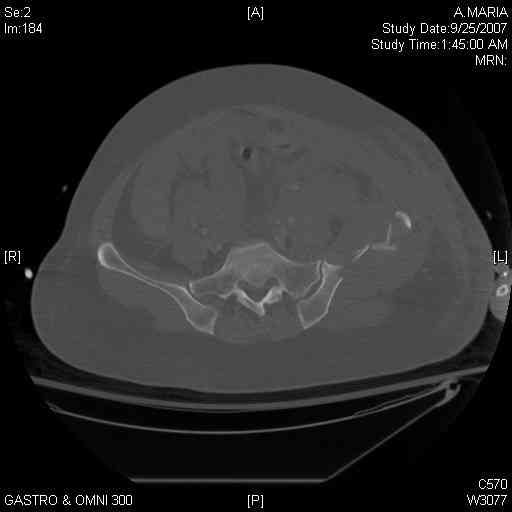

[Ortho] comminuted crescent fx

Any advice would be appreciated:

40 ish female ejected from car. Unstable, DPL negative, went to angio and had her pelvic bleeds embolized after many units of blood. GCS 6, floating elbow, clavicle, bothbones, etc.

My standard approach to  this pelvis would be posterior, reduce/lag/plate  thecrest, reduce/plate the caudal extent on the posterior crest and 1-2 lags back to front. In this case, the crest comminution seems to make plating all

the way to the ASIS useless, as the plate would be on free floating fragments. Would plating the posterior extent of the fracture to secure the

reduction at the SI joint and 2 screws back to front be sufficient fixation? Would anyone do a perc reduction and perc back to front screws, and would that be sufficient if the SI joint could be reduced (although I don't see how this could be accurately reduced closed). Would an ilioninguinal with a pelvic brim plate and posterior column screws be a better approach, although reducing the SI would be more indirect and less accurate?